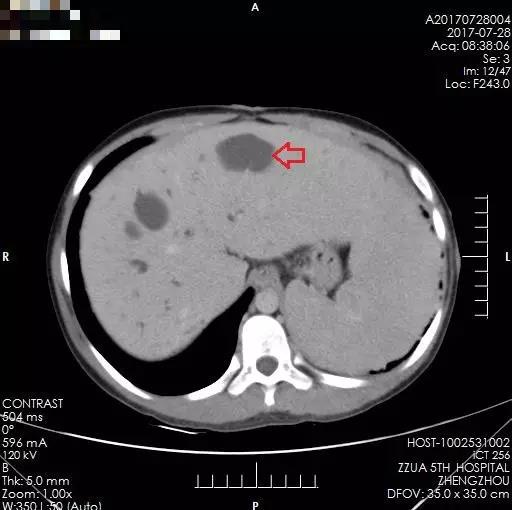

李晓勇教授及主管医生陈艳军副主任医师热情地接待了小夏及家人,在全面了解病史、详细检查之后,小夏的病情让经历了种种疑难病症的李晓勇教授陷入了深思。小夏的肝脏明显增大,弥漫性肝硬化,肝中叶肿物较大,80mm×70mm左右,并且肿物与左右肝管关系密切,门静脉主干及左右支明显受压。

术前肝肿瘤